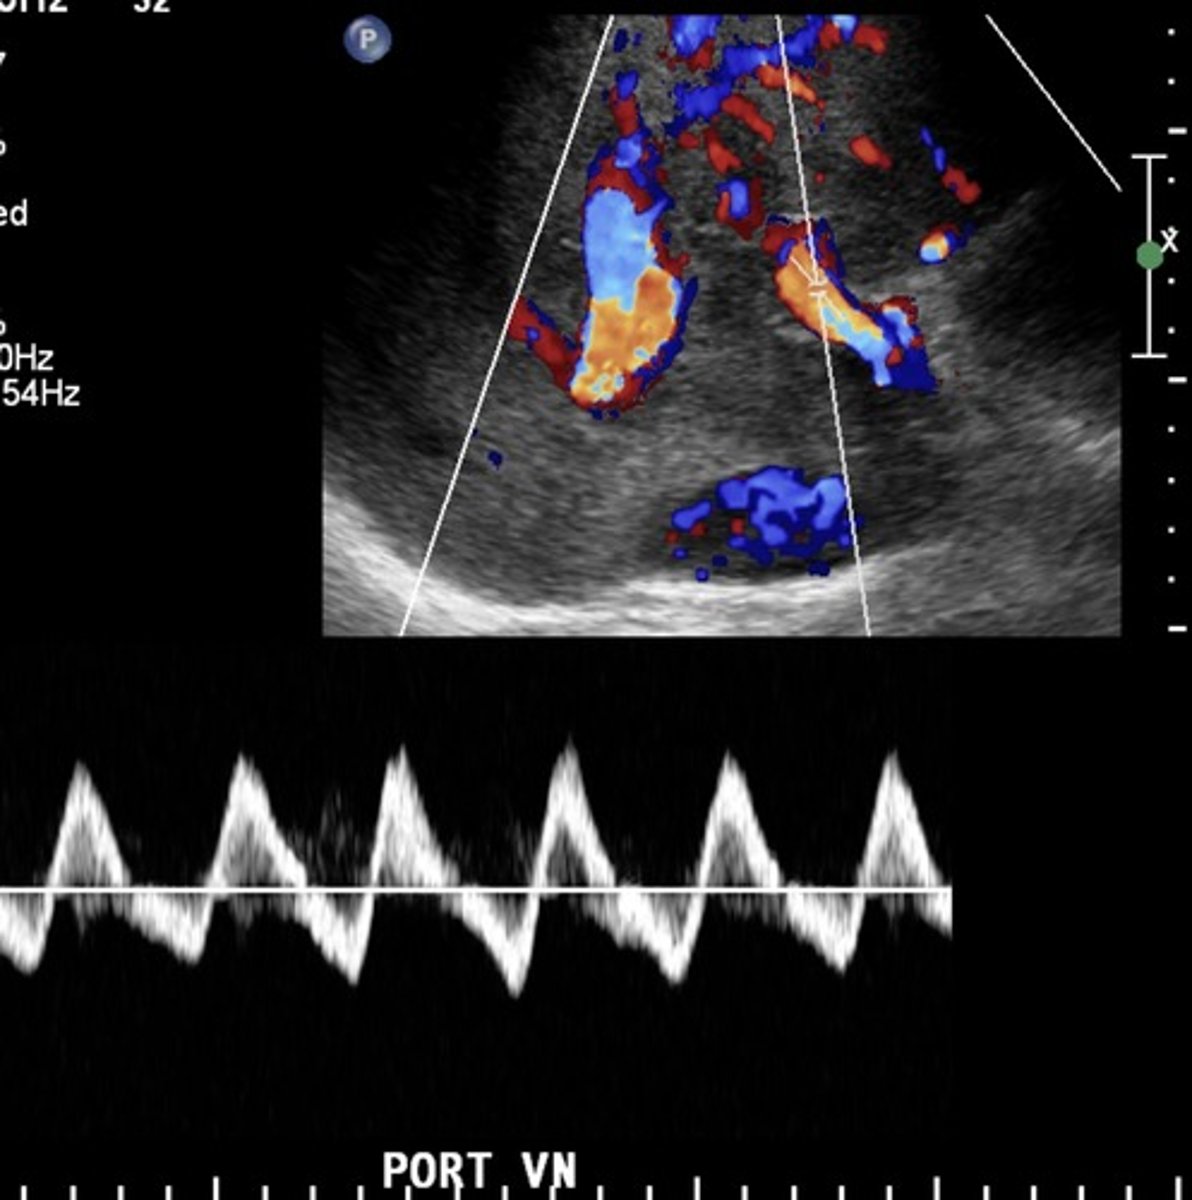

Portal Vein with Cardiac Cirrhosis

Pulsatile

Biphasic

Hepatic Veins with Cardiac Cirrhosis

Compromised flow - over congestion

"w" pattern